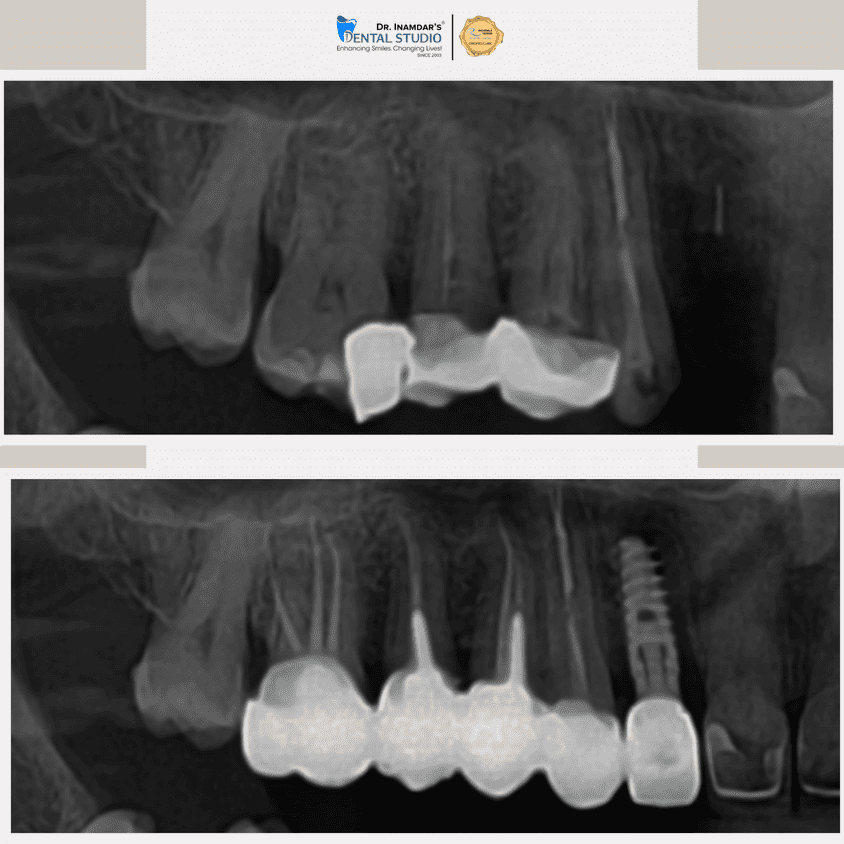

We begin with a detailed dental examination and digital X-rays to identify the source of infection.

The infected tissue is gently removed, and the tooth is thoroughly cleaned and disinfected.

The tooth is sealed and usually protected with a crown to restore strength and function.